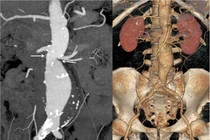

Đặt stent graft điều trị phình động mạch chủ bụng nguy kịch

Thay vì phải mở bụng, đặt stent graft giúp rút ngắn quá trình can thiệp, giảm mất máu, nguy cơ biến chứng thấp, thời gian nằm viện chỉ vài ngày.